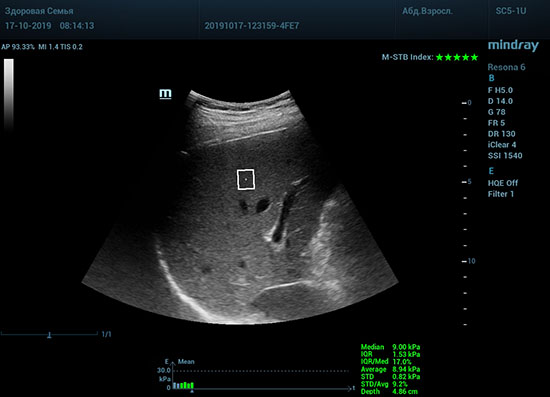

Определение плотности печени. Не ошибся ли оператор при измерении эластических свойств печени? Для оценки критериев качества предусмотрен индекс MBT, который покажет насколько «твердой» была рука оператора и двигалась ли печень. При MBT 5* рука тверда и показатели достоверны. Для оценки качества результатов используется IQR индекс, отображающий колебания показателей в точке измерения при расчете медианы. Показатели при IQR <30% считаются приемлемыми. Техника сканирования через межреберные промежутки требует размещение окна интереса на несколько сантиметром ниже капсулы, для исключения эффекта реверберации. Установка ROI на паренхиму без захвата сосудов, для исключения погрешностей измерения.